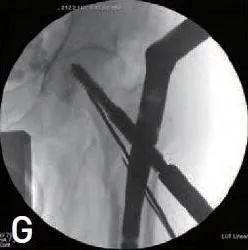

下一步是插入拉力螺钉(图 1G)。因此,需要检查C 型臂扫描的AP和侧位的髓外复位情况。锁定拉力螺钉,然后插入远端锁定螺钉和端盖。

图1G 插入拉力螺钉以维持髓外复位。